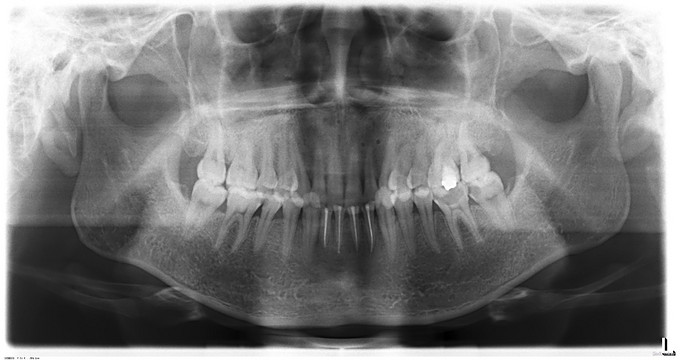

头颅无畸形。张口度3.5cm,开口型↓,关节区无疼痛、弹响。口内检查:中线口腔卫生良好,上颌牙齿无松动,下颌31、32、41、42冠折后根管治疗术后,无松动,后牙咬合可,36深龋。口内黏膜无异常。

X-ray示:上颌骨钛板全部拆除, 出院带药:甲钴胺片 0.5mg*24# sig:0.5mg po tid 2.保持口腔卫生,饭后漱口; 3.一周后口外门诊复诊拆线; 4.定期复诊,不适随诊。